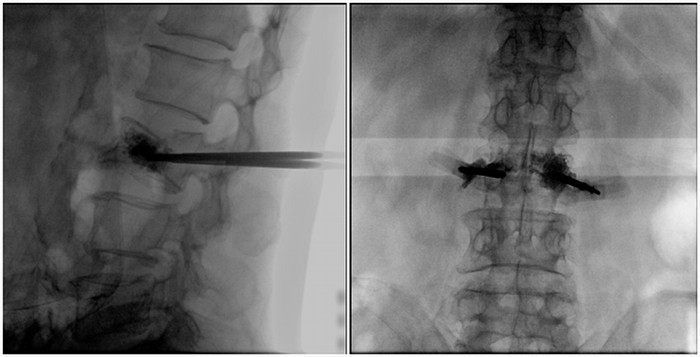

術(shù)中切口5毫米,在大平板C臂機(jī)的透視指引下,確定了進(jìn)針的方向及進(jìn)針的深度。經(jīng)椎弓根向椎體置管,建立通道,插入骨擴(kuò)張器(球囊)。球囊擴(kuò)張恢復(fù)椎體高度,并在椎體內(nèi)形成空腔,確定骨水泥的注入劑量,并注入骨水泥觀察其擴(kuò)散情況。

大平板C臂機(jī)臨床圖像

市面上主流的小C大多采用21CM×21CM的平板或者影像增強(qiáng)器,成像范圍較小,一般可成像3.5節(jié)腰椎,確定傷椎可能需要進(jìn)行多次拍攝。普愛醫(yī)療大平板C臂機(jī)采用30CM×30CM的平板探測器,一般可一次性成像5節(jié)腰椎,呈現(xiàn)更廣闊的視野。使醫(yī)生一次性全面地觀察到傷椎及周圍椎體情況,使得手術(shù)效率更高、更準(zhǔn)確。如果您想采購,或了解這款大平板C臂機(jī)技術(shù)參數(shù),歡迎咨詢400-025-6366。